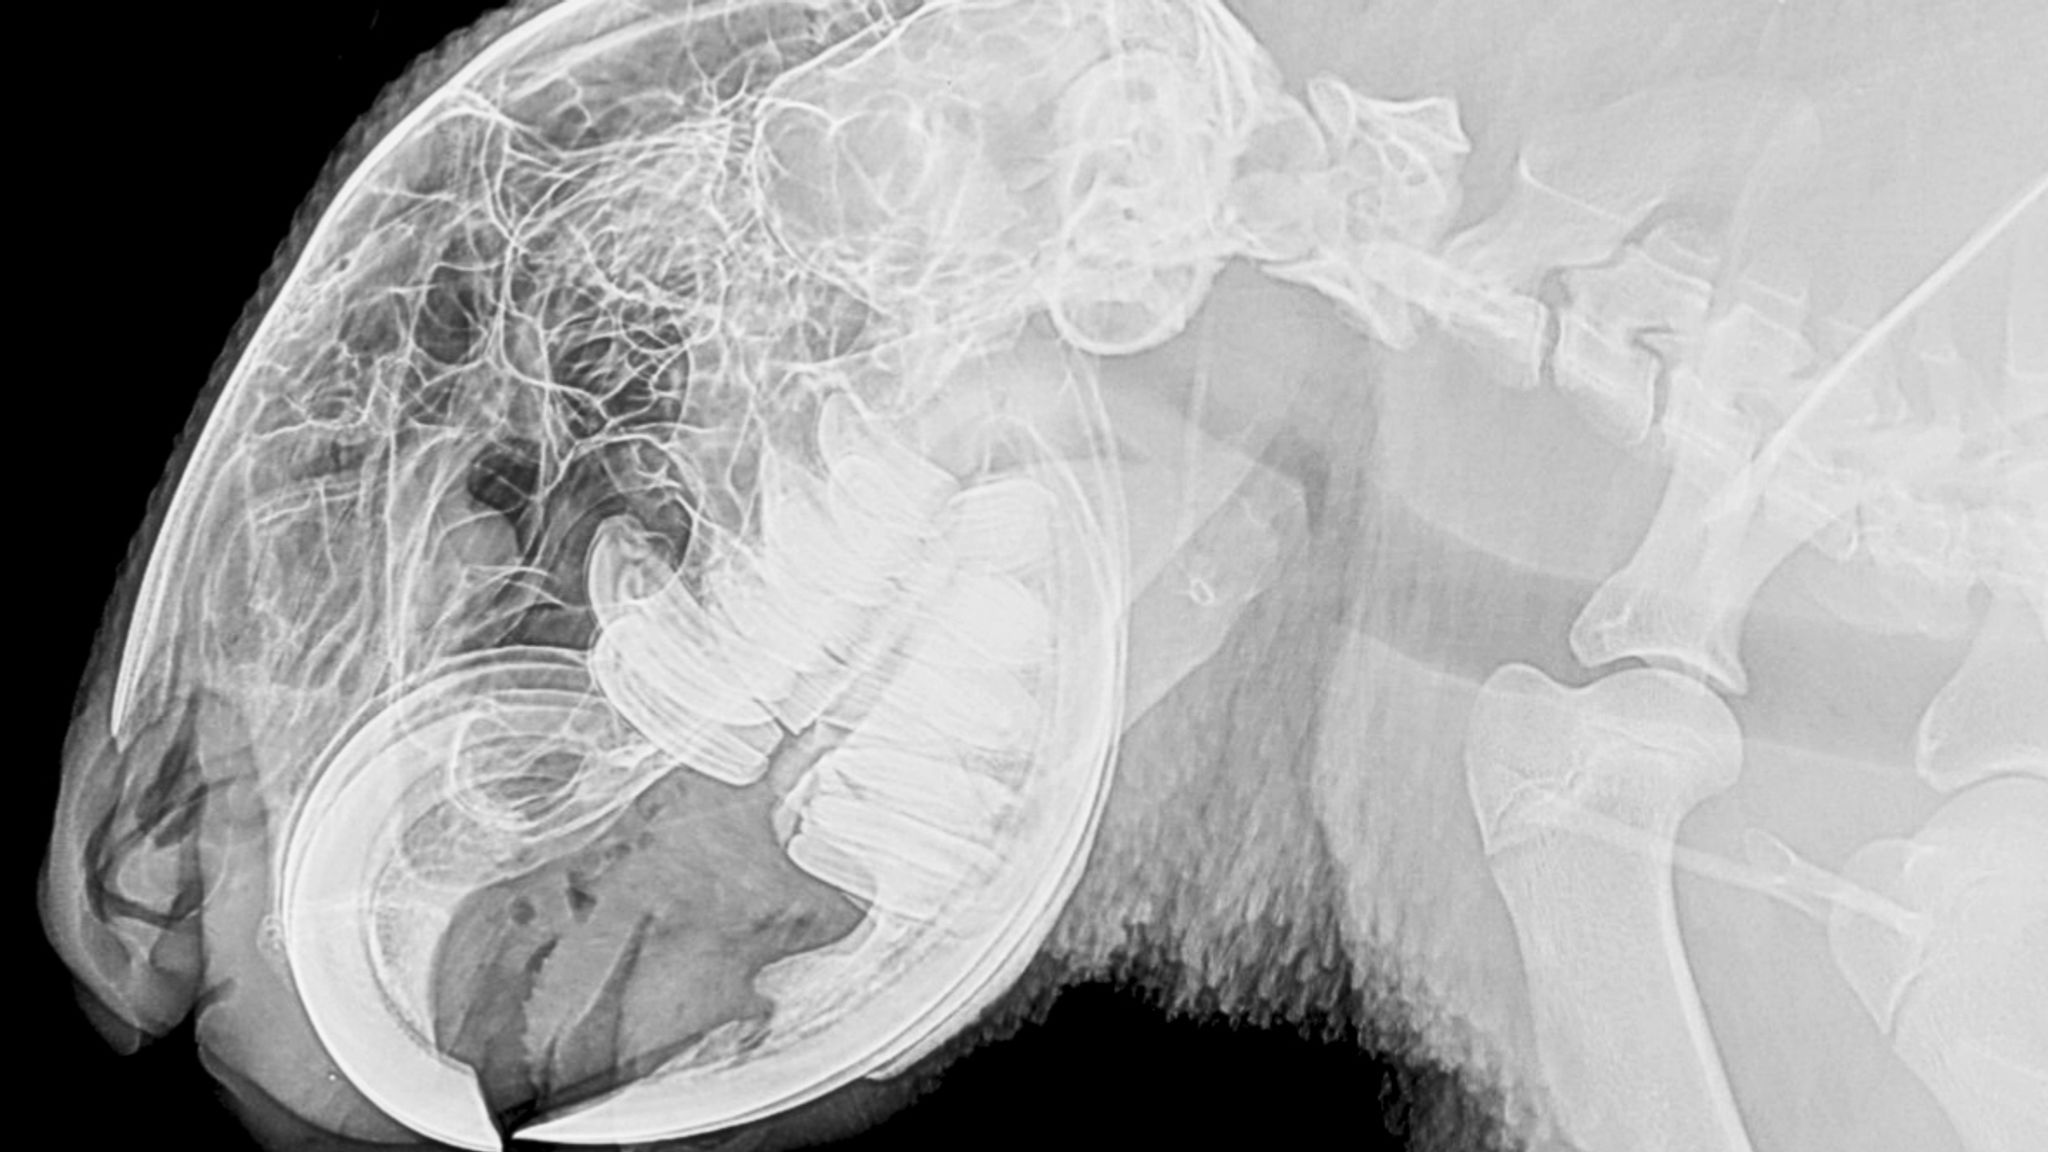

X ray horse

X ray horse 133 фото